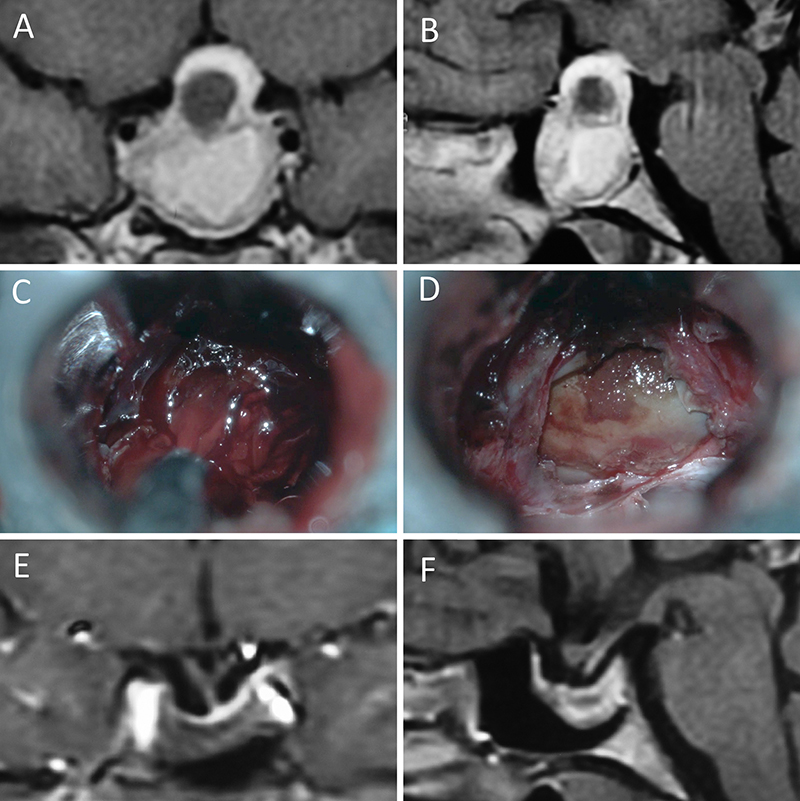

Figura 5: Apoplejía hipofisaria hemorrágica en un hombre de 32 años. El paciente presentó cefalea y parálisis completa del III par. Tuvo restitutio ad integrum en el seguimiento. A-B: RM preoperatoria; C-D: intraoperatorio; E-F: RM postoperatoria.

Figura 6: Apoplejía hipofisaria hemorrágica en un hombre de 55 años. El paciente presentó cefalea, déficit visual y parálisis completa del III par. Evolucionó favorablemente tras la cirugía, revirtiendo el cuadro. A-B: RM preoperatoria; C-D: intraoperatorio; E-F: RM postoperatoria.